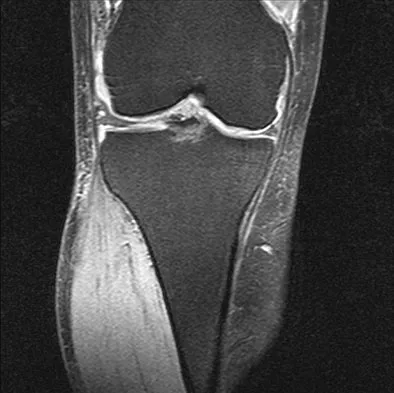

A 40-year-old woman reports the atraumatic onset of severe knee pain and swelling after undergoing an uncomplicated elective cholecystectomy 1 week ago. She denies any history of diabetes mellitus or HIV but has had occasional episodes of mild knee pain and swelling that have always responded to nonsteroidal anti-inflammatory drugs. Radiographs are shown in Figures 5a and 5b. A knee aspiration yields a WBC count of 35,000/mm3. The aspirate should also yield which of the following findings?

Explanation

The radiographs reveal chondrocalcinosis of the menisci. This is caused by calcium pyrophosphate crystals, which are weakly positive birefringent rhomboid-shaped crystals. Frequently, this condition is asymptomatic; however, routine abdominal surgery may cause precipitation of these crystals and pain. Gout, which is caused by strongly negative birefringent needle-shaped sodium urate crystals, is not associated with chondrocalcinosis and is rare in younger women. Gross blood is uncommon without trauma. Infection is not likely in a healthy patient who underwent uncomplicated surgery. Fisseler-Eckhoff A, Muller KM: Arthroscopy and chondrocalcinosis. Arthroscopy 1992;8:98-104.